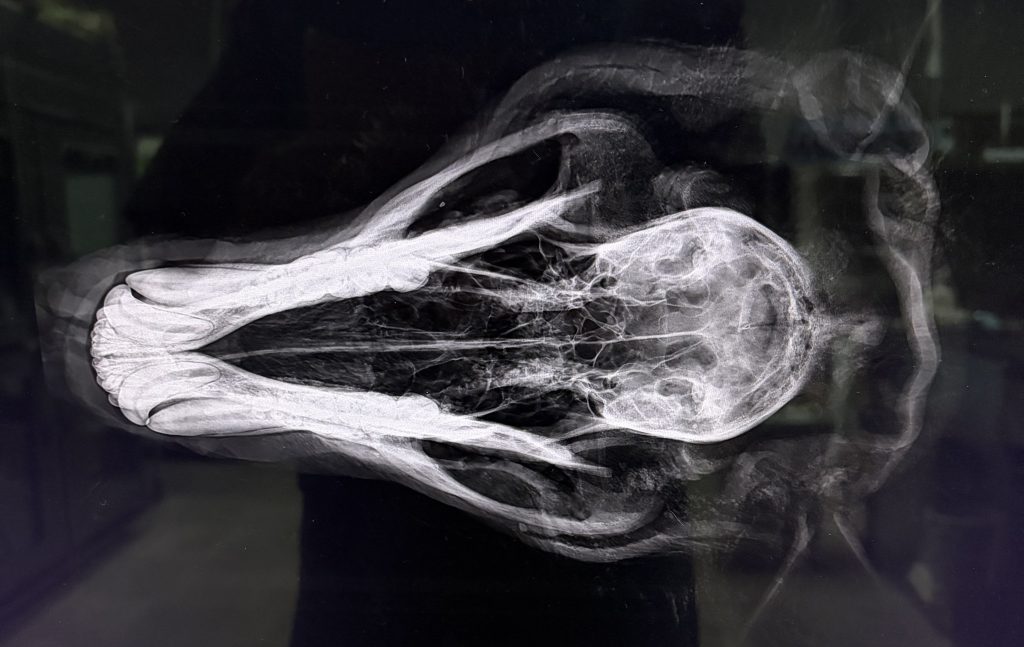

標本作る前に、骨学のために、

レントゲン検査

横と、縦から撮影

まだまだ若そうな歯をしています

歯は丈夫そう

何でも食いちぎる筋肉もあります

クマのレントゲンは初めて撮影、

初めて診たっ